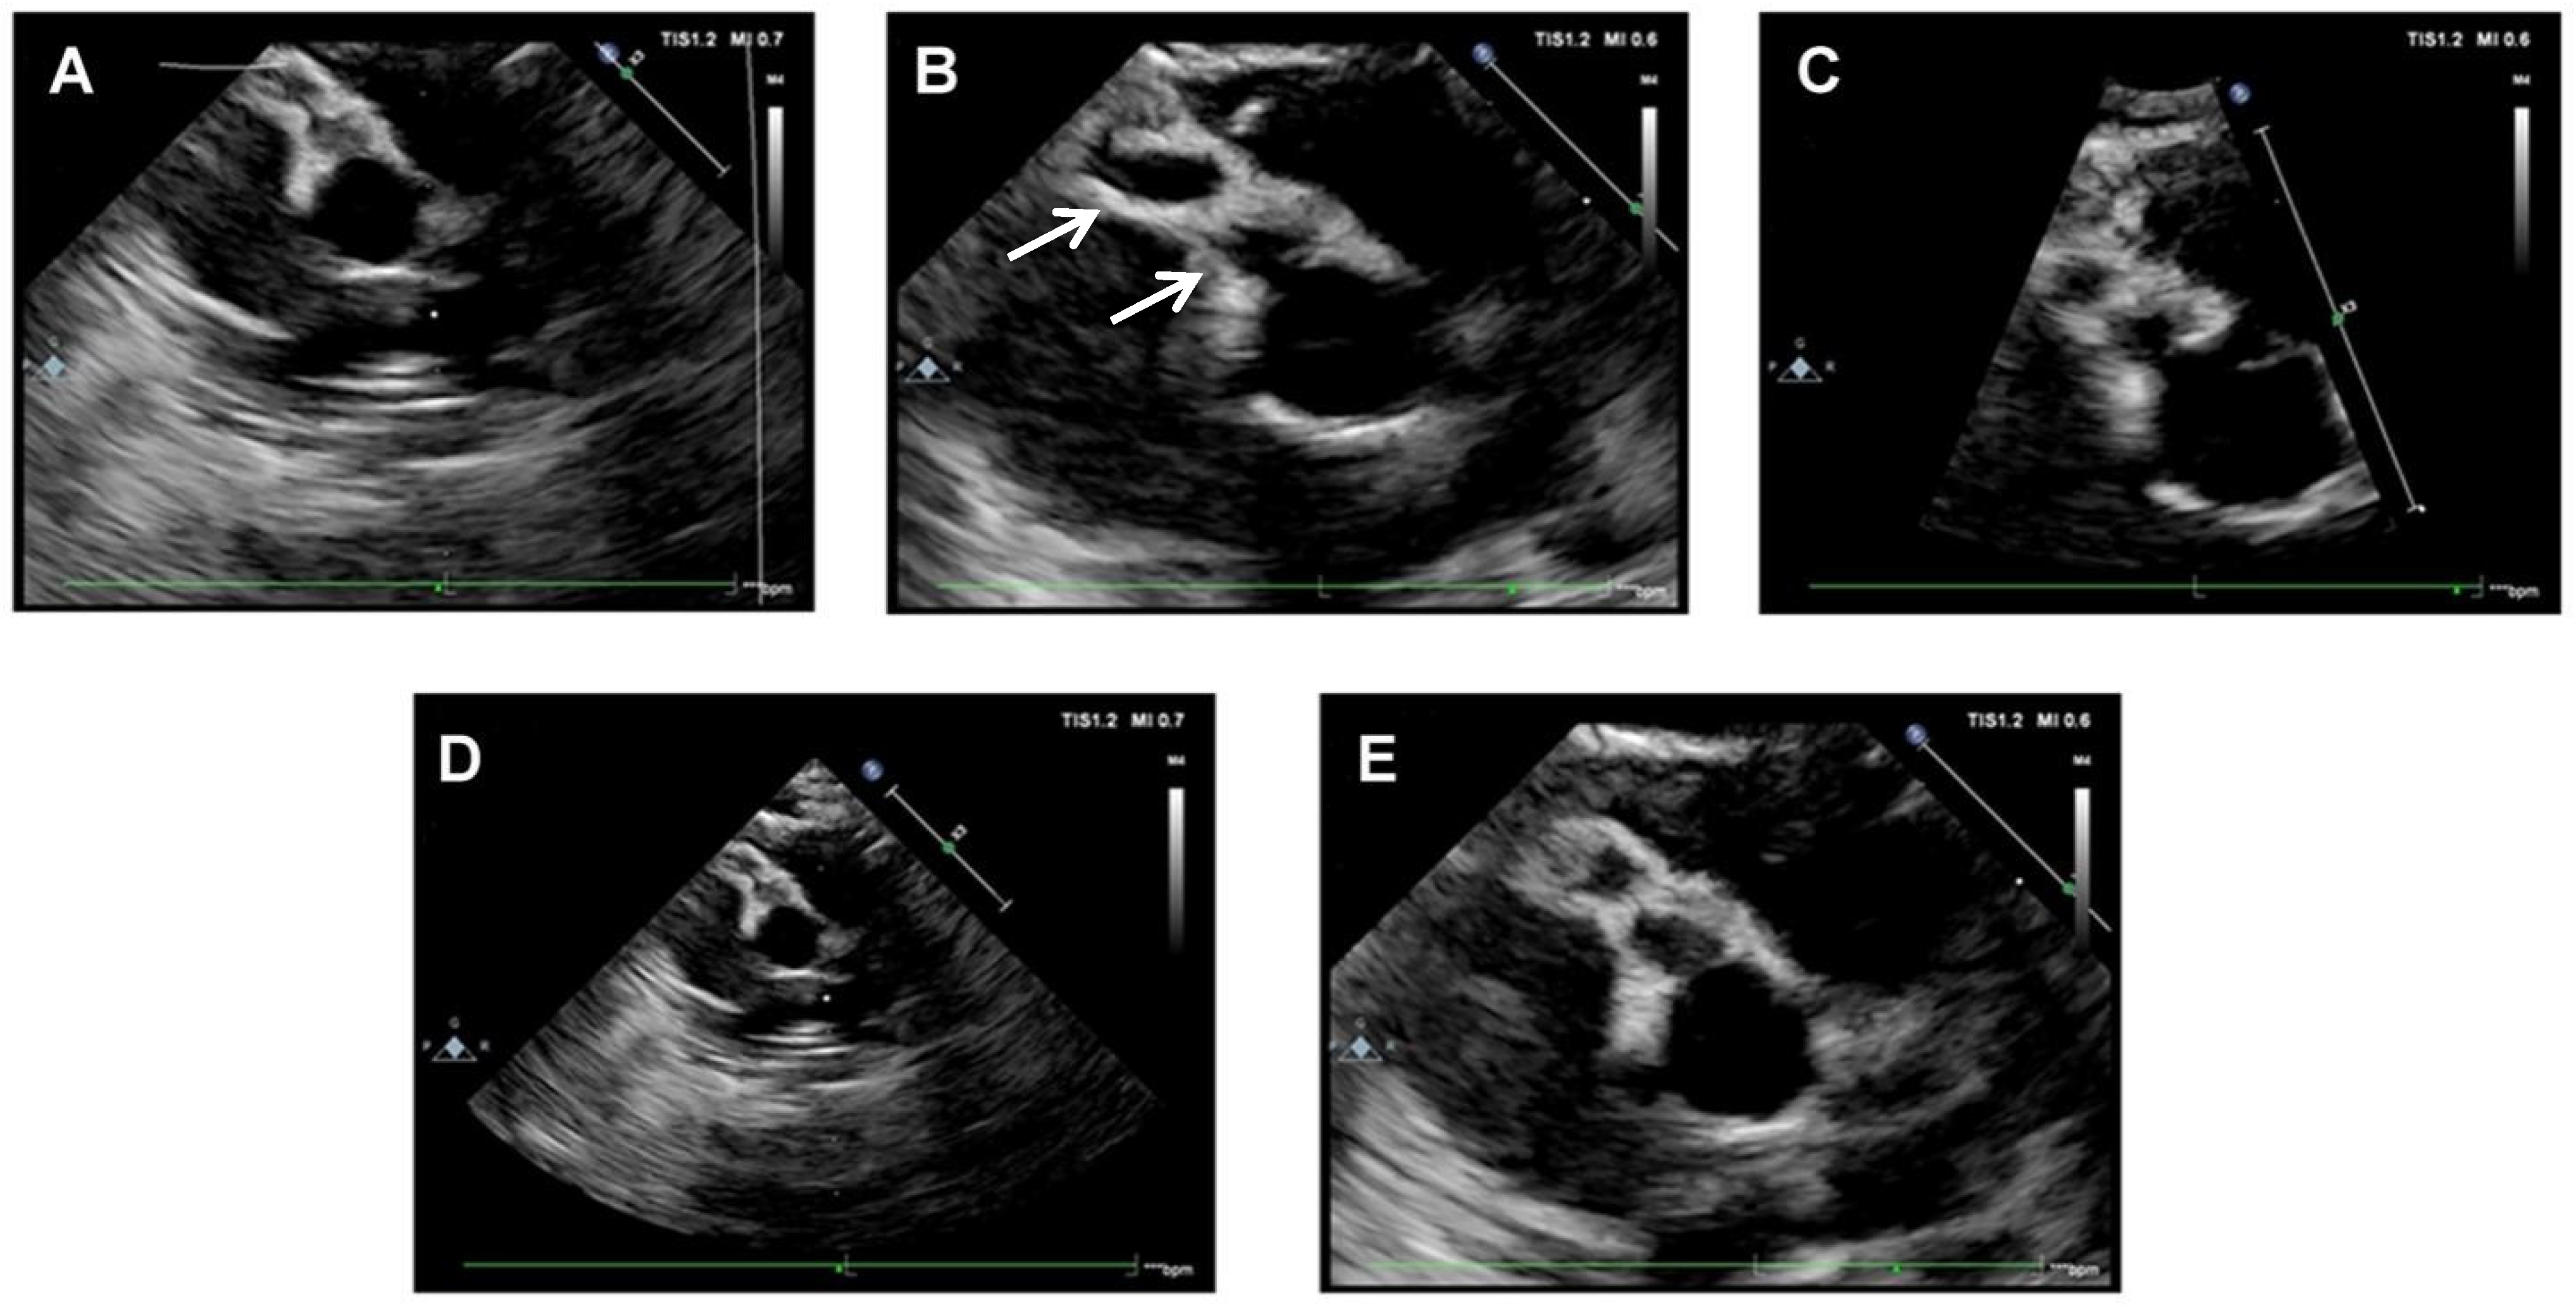

2. Case Presentation